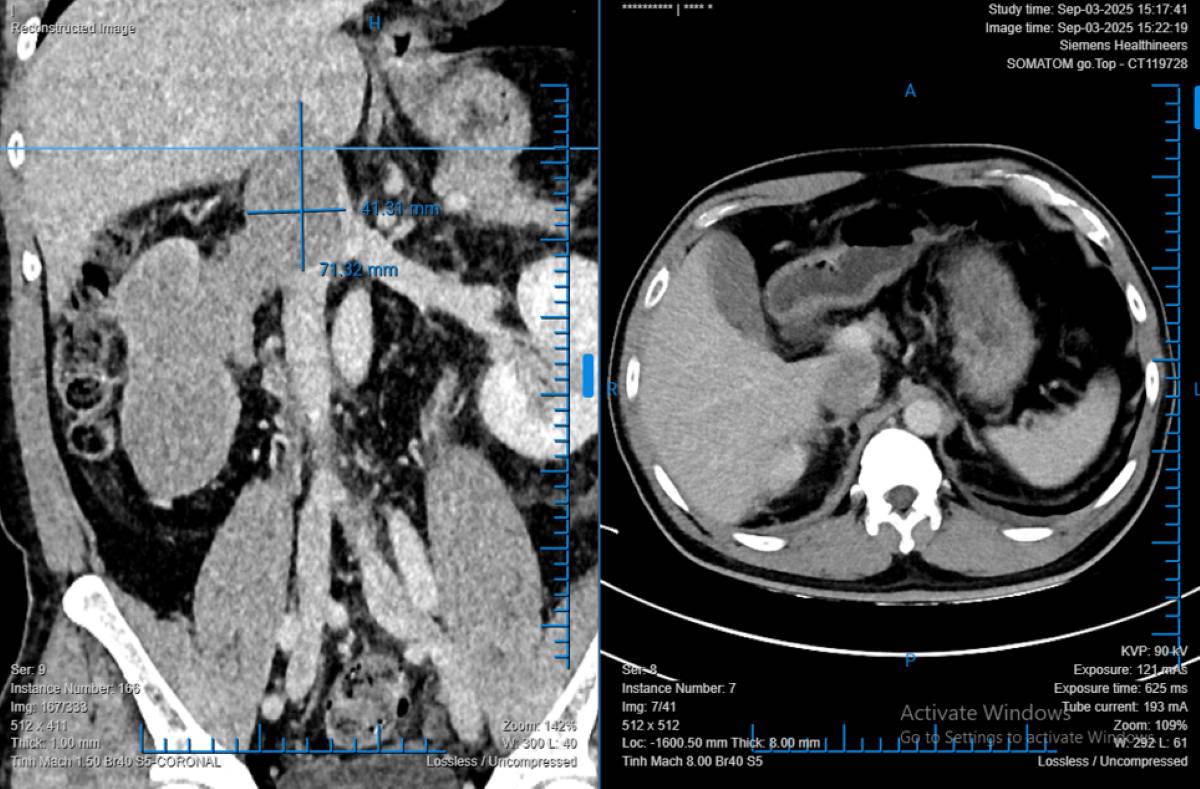

Mr. T.D.L (48 years old, Quang Tri) discovered kidney disease during a regular health check-up. When examined at Binh Dan Hospital, the imaging diagnostic results showed that the tumor occupied almost the entire right kidney, measuring 68x86x138 mm, with thrombosis spreading deep into the kidney vein and lower main vein.

Dr. Pham Phu Phat - Head of Nephrology A Department of Binh Dan Hospital shared that this is a case of renal cell carcinoma (RCC) with a tumor of up to 76 mm, the largest of all cases that he has ever had surgery. The average life expectancy of patients is only about 5 months if not treated promptly.